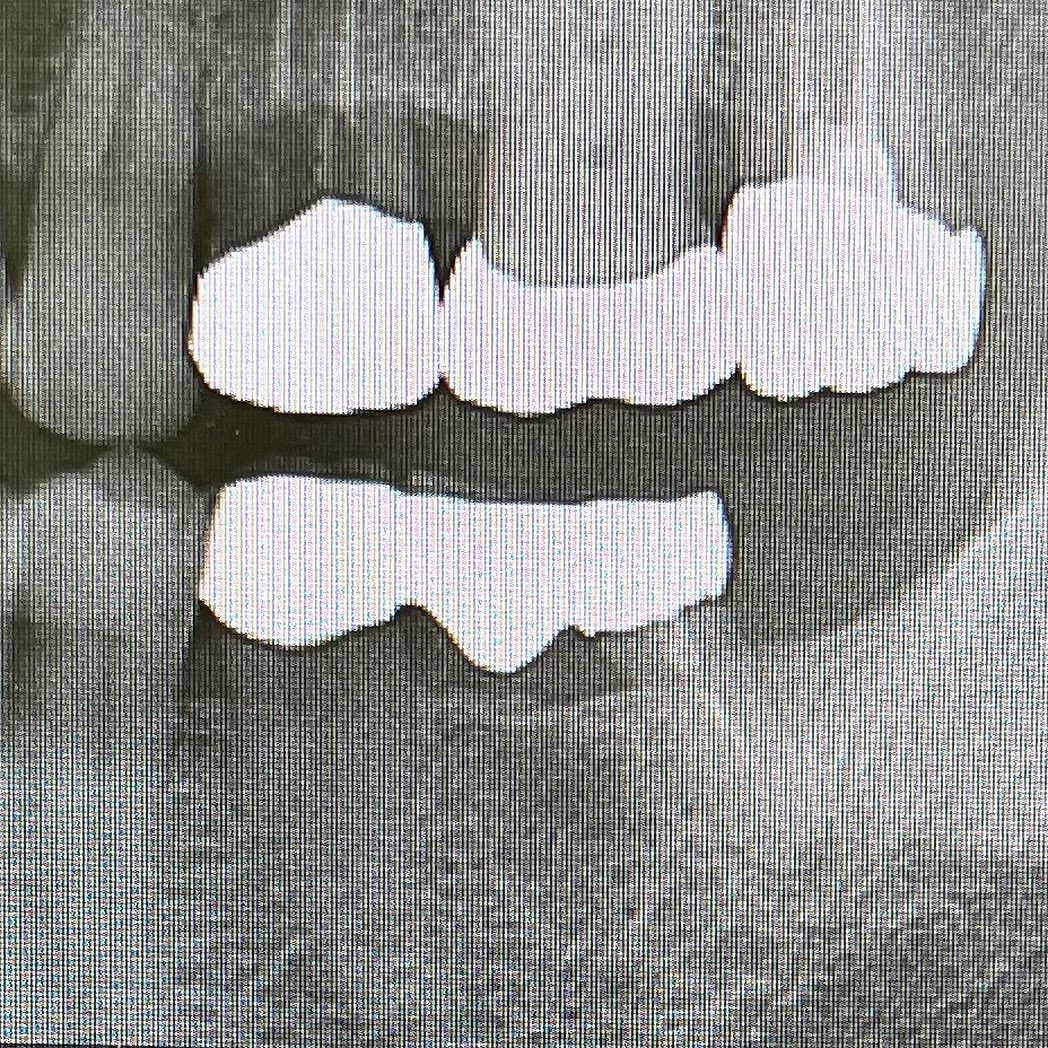

歯根肥大とアンキローシスに苦しめられましたが無事抜歯(40分😭)し、ソケット近心と遠心にDENSAH BURにてOsseodeficationするようCCW(逆回転)➡️前後からソケット方向に骨を拡張して、ソケットサイズダウンしつつ、インプラントフィクスチャー全周囲を既存骨内に埋入できました。🟢🟡矢印が寄せた既存骨です。

36→ARφ5.5×10.0mm【75/75】

37→ARφ5.0×8.5mm【75/75】

ISQも高く即時荷重しても良いくらいでしたが、今回はφ4.0×4.0のHealing Abuttmentを装着した一回法。歯肉より4mm縁下にプラットフォームが位置することを考えるとHAが4mmなのは目で分かるので良いですね。理にかなってます。